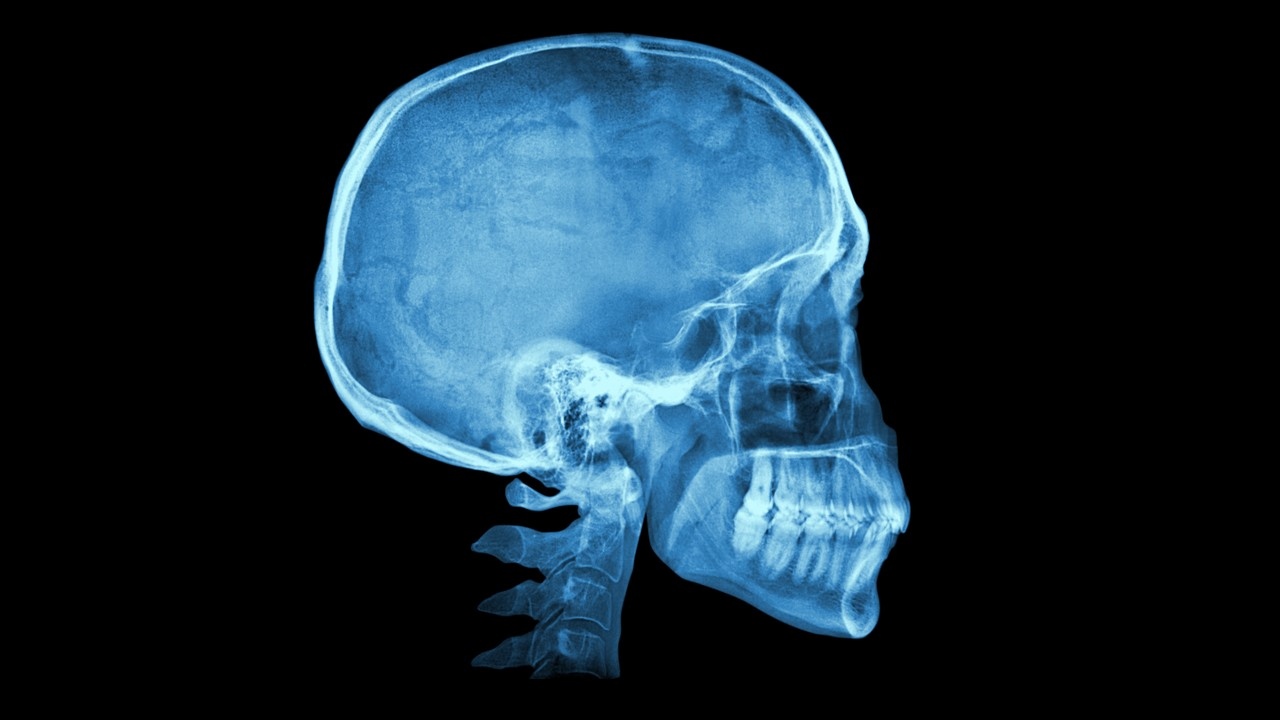

De ’slaap’ ligt aan de zijkant van ons hoofd, ongeveer daar waar de wenkbrauw eindigt. Dit wordt beschouwd als het zwakste deel van onze schedel, maar waarom?

Precies op deze plek blijken vier schedelbeenderen samen te komen: het voorhoofdsbeen, het wandbeen, het slaapbeen en het wiggenbeen, waardoor dit gebied relatief breekbaar is. Bovendien loopt onder deze botten een belangrijke slagader: de middelste meningeale slagader. Die levert bloed aan de buitenste laag van de hersenen, de hersenvliezen.